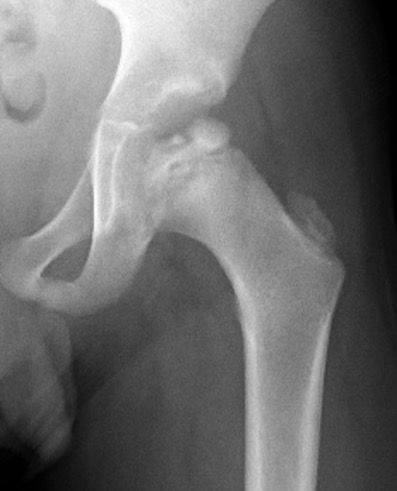

Waldenstrom Stages

1. Initial

Duration : 3- 6 months

Xray

- may be normal

- small, sclerotic epiphysis

- joint space widening

- increased density of ossific nucleus & cessation of growth

2. Resorption / fragmentation

Duration : 6/12

Pathologic Process

- necrotic bone irregularly resorbed / creeping substitution

- replaced with vascular fibrous tissue

- may be associated with collapse

XRay - Fragmentation of Physis